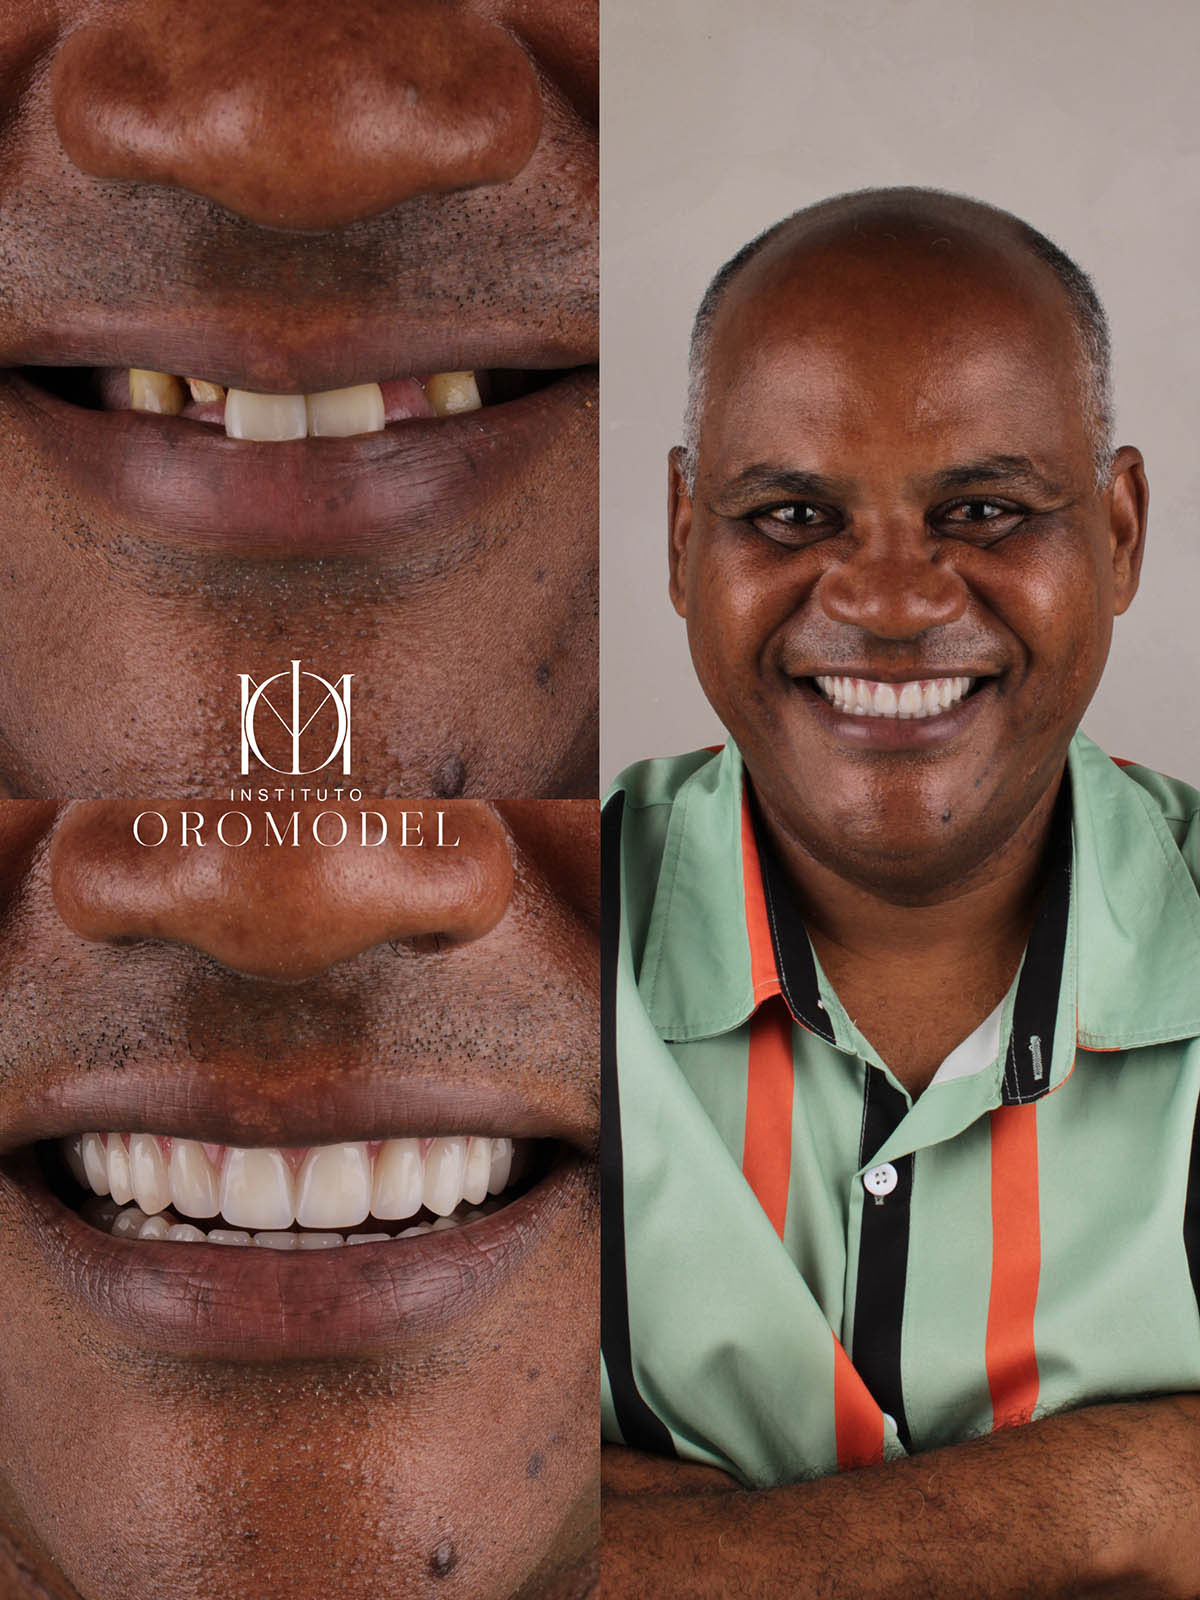

Protocolo Sobre Implantes

Prótese fixa sobre implantes. Uma solução para quem usa dentadura ou perdeu grande parte dos dentes.

Prótese fixa sobre implantes. Uma solução para quem usa dentadura ou perdeu grande parte dos dentes.

A reabilitação oral por meio de implantes osseointegráveis é uma forma prática e segura de repor a falta de dentes, corrigindo a estética bucal e a função mastigatória.

Artistas, executivos, profissionais liberais e empresários, para os quais a aparência é necessária e requisitada, têm-se beneficiado muito com essa técnica revolucionária que vem sendo executada e melhorada em seus quase 50 anos de estudo. As técnicas estão cada vez mais avançadas e permitem ao paciente adquirir próteses fixas imediatas. Para o sucesso do tratamento são fundamentais habilidade, bom-senso, tecnologia e experiência profissional.

Hoje temos o conhecimento que o osso alveolar (osso que envolve a raiz do dente) sofre reabsorção devido à falta de estímulo após a retirada do dente. Em casos em que o paciente perdeu dentes há muito tempo, associado ao uso da dentadura “frouxa” (desadaptada) essa reabsorção do osso que fica embaixo da gengiva é geralmente maior, dificultando a confecção de uma nova dentadura, que em muitos casos é bem solucionada quando fazemos implantes.